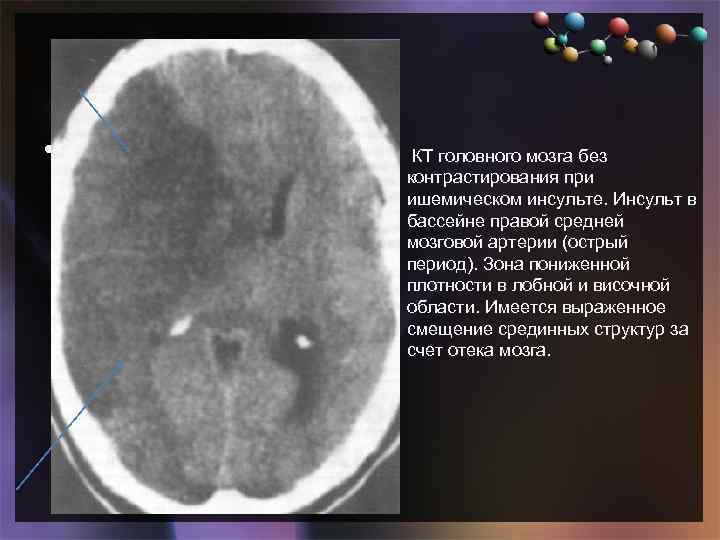

Иллюстрации и пояснения: гиподенсивный очаг на КТ головного мозга

Раздел: Кадры перемен